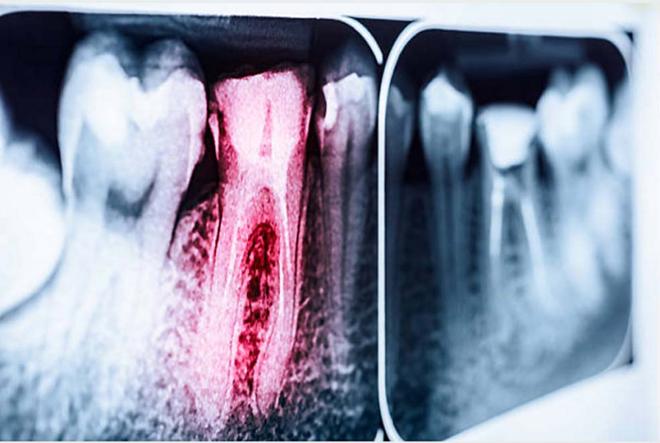

Una endodoncia en un diente con más de dos conductos pulpares recibe el nombre de endodoncia multirradicular.

Un endodoncista es un dentista experto en los tratamientos de endodoncia, también llamados de conductos radiculares.

Los postes de fibra para endodoncia son fundamentales para reconstruir dientes que han sido muy dañados por la caries.